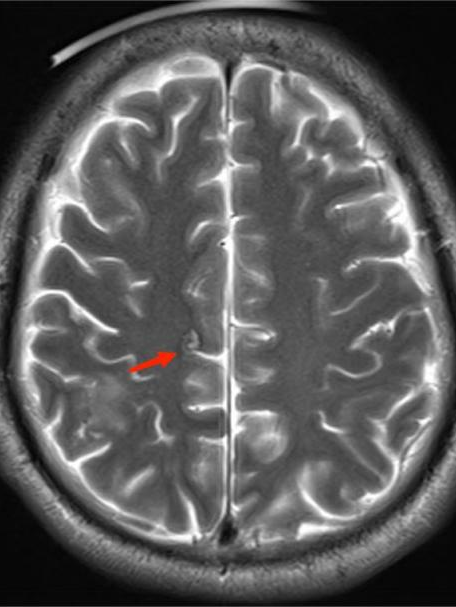

得到这条线索后,ICU 医生立即为李先生进行一系列脑部检查。最终,李先生头颅 MR 显示其脑内有寄生虫感染!明确诊断为脑囊虫病!